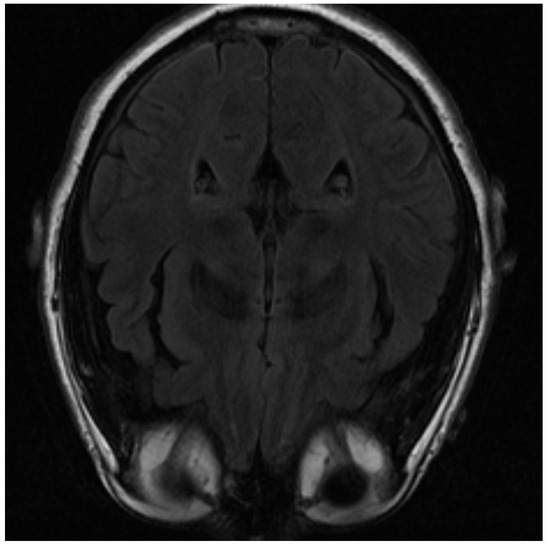

One of the images used in the simulations is shown in Figure 3. The image corresponds to an axial section of the brain in the plane marked by the blue lines in Figure 4. In it, the orbit of the eyes can be distinguished in the lower part. Fat appears with a very strong signal, while water and cerebrospinal fluid have a very low intensity.

The image is blurred in the left orbit, which is an example of an artifact. An artifact is a distortion in the image that has no relation to the subject of the studied body region. In this case, it is generated by the movement of the patient [44]. Artifacts must be recognized, as they can simulate non-existent medical conditions or cover up real problems. In this case, its origin is clear, but in general, it is necessary to know the different types of artifacts that can be produced in order to be able to distinguish and address them properly. The impact of artifacts on the reconstruction process depends on their size. If the artifact is not too large, reconstruction can smooth it out and produce an image without its effect. In this sense, the best algorithm that can deal with artifacts is PD because it leads to clearer and blur-free images as will be seen.

Figure 3. MRI image of an axial slice of the brain. In the area below are the eye orbits [15].